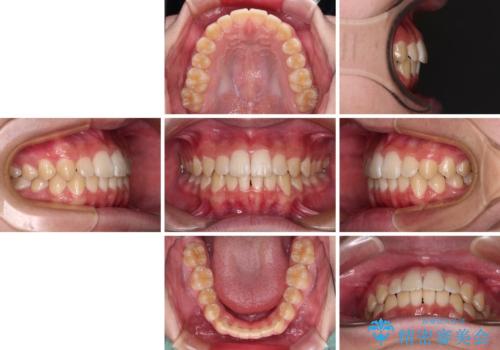

「しっかりと装着する」が実行でき、高校3年生の秋には治療を終えることができました。

入試時期に入ると、後戻り防止のリテーナー装着が疎かになる可能性があったり、リテーナーが壊れてしまった場合すぐに来院できなかったりというリスクがあったため、下顎前歯の舌側をワイヤーで固定することとしました。